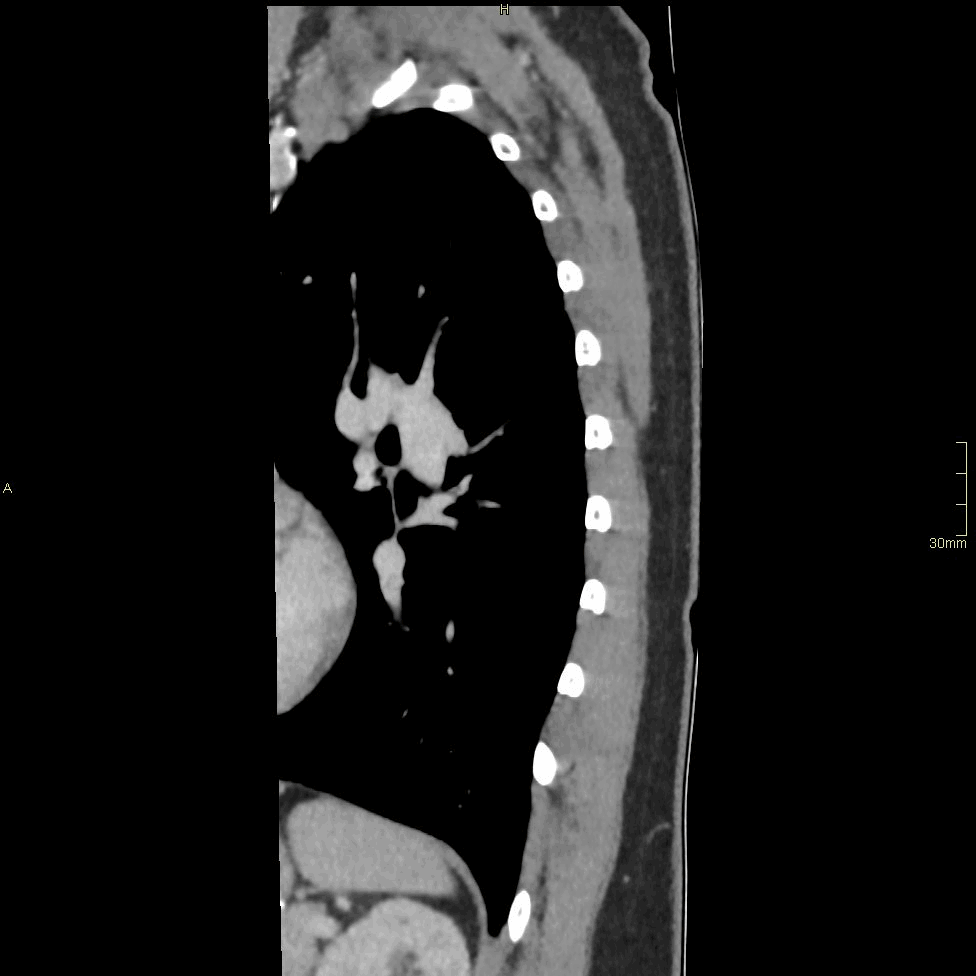

CT Thoracic Spine Contrast- Soft tissue window (sagittal)